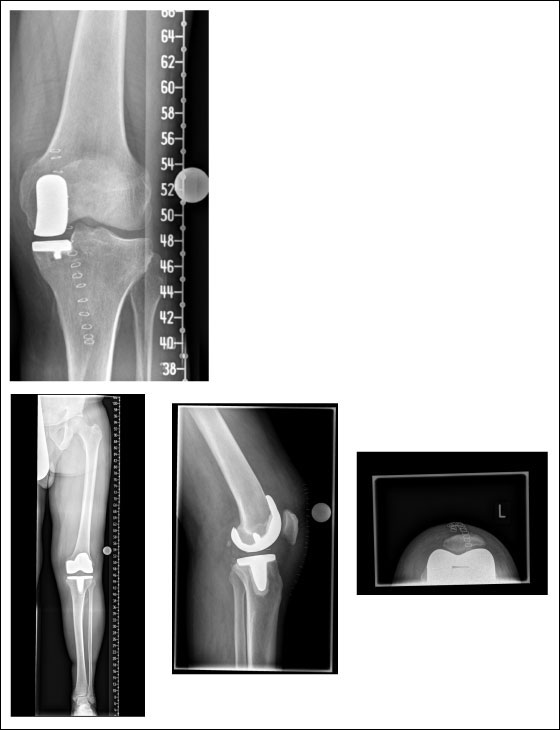

Abbildung 3

Abb. 3 (anklicken zum Vergrößern): Oben: Unikompartimenteller Ersatz des Kniegelenks: „mediale Schlittenprothese“. Nur der verschlissene Anteil des Kniegelenks wird ersetzt, der gesamte Bandapparat des Kniegelenks kann erhalten bleiben.

Unten: Röntgenbild eines Oberflächenersatzes („LCS“-Knieprothese).